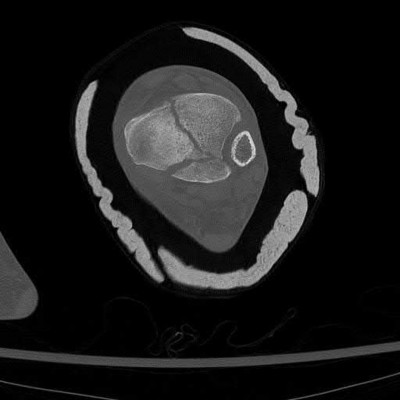

Figure C is an axial CT scan of a lateral compression type 3 (LC3) pelvic ring injury.

Classically, LC3 injuries demonstrate an ipsilateral lateral compression and a contralateral APC (windswept pelvis) fracture pattern. The most common mechanism of injury in these cases is a rollover MVC or pedestrian vs. auto. LC1 injuries are characterized by an oblique or transverse ramus fracture and ipsilateral anterior sacral ala compression fracture, while LC2 injuries consist of a rami fracture and ipsilateral posterior ilium fracture dislocation (crescent fracture). While LC1 injuries can often initially be managed conservatively with protected weight-bearing and close observation, LC2 and LC3 pelvic ring injuries are almost universally operative.

Pennal et al. discuss a radiologic technique for assessing the forces producing pelvic disruption and its use in logically classifying pelvic injury. Based on this radiologic assessment and along with some biomechanical studies, they propose a classification system involving three major forces producing injury that can also be helpful in the management of these patients.

Young et al. performed a retrospective analysis of the plain radiographs of 142 cases of pelvic fractures and identified four patterns of force that presented with distinctive, recognizable radiographic appearances. They describe a classification system for pelvic fractures based on radiographic and clinical findings that correlates with associated injury to soft-tissue structures and enables the surgeon to begin corrective procedures rapidly.